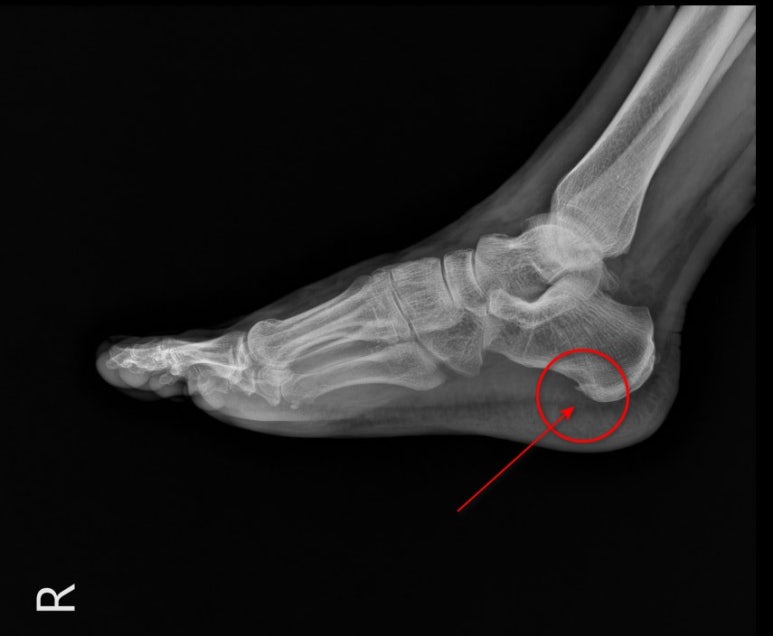

위 사진처럼

엑스레이에서는

근막의 경계가 보이지 않아

정확하게 진단할 수 없습니다.

이 맞는지확인하려면초음파 검사를해봐야 하는 것이죠.